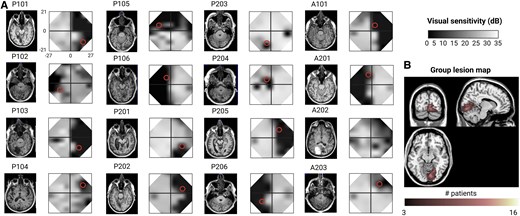

To enhance the effects of such rehabilitation programmes, we designed a novel, non-invasive, pathway-specific, physiology-inspired cross-frequency brain stimulation protocol, where complex oscillatory signal integration was inferred from phase–amplitude coupling of oscillatory signals between the primary visual cortex and the motion-sensitive medio-temporal area. Sixteen stroke patients were enrolled in a double-blind, randomized, cross-over trial, during which they performed two blocks of 10 daily training sessions of a direction discrimination task, combined with one of the two cross-frequency transcranial alternative brain stimulation (cf-tACS versus control cf-tACS) conditions.

We found that the cf-tACS condition promoting feedforward visual inputs to the medio-temporal area significantly enhanced motion discrimination performance and shifted visual field borders (i.e. through localized enlargement of isopters). Behavioural improvements associated with a change in oscillatory activity within motion processing pathways were proportional to the amount of residual structural fibres along these pathways and perilesional primary visual cortex activity. In sum, we report, for the first time, that cf-tACS, a novel, pathway-specific, physiology-inspired brain stimulation approach, is able to boost the efficacy of perceptual training, restoring visual motion processing and reducing the severity of visual impairments in adult stroke patients.